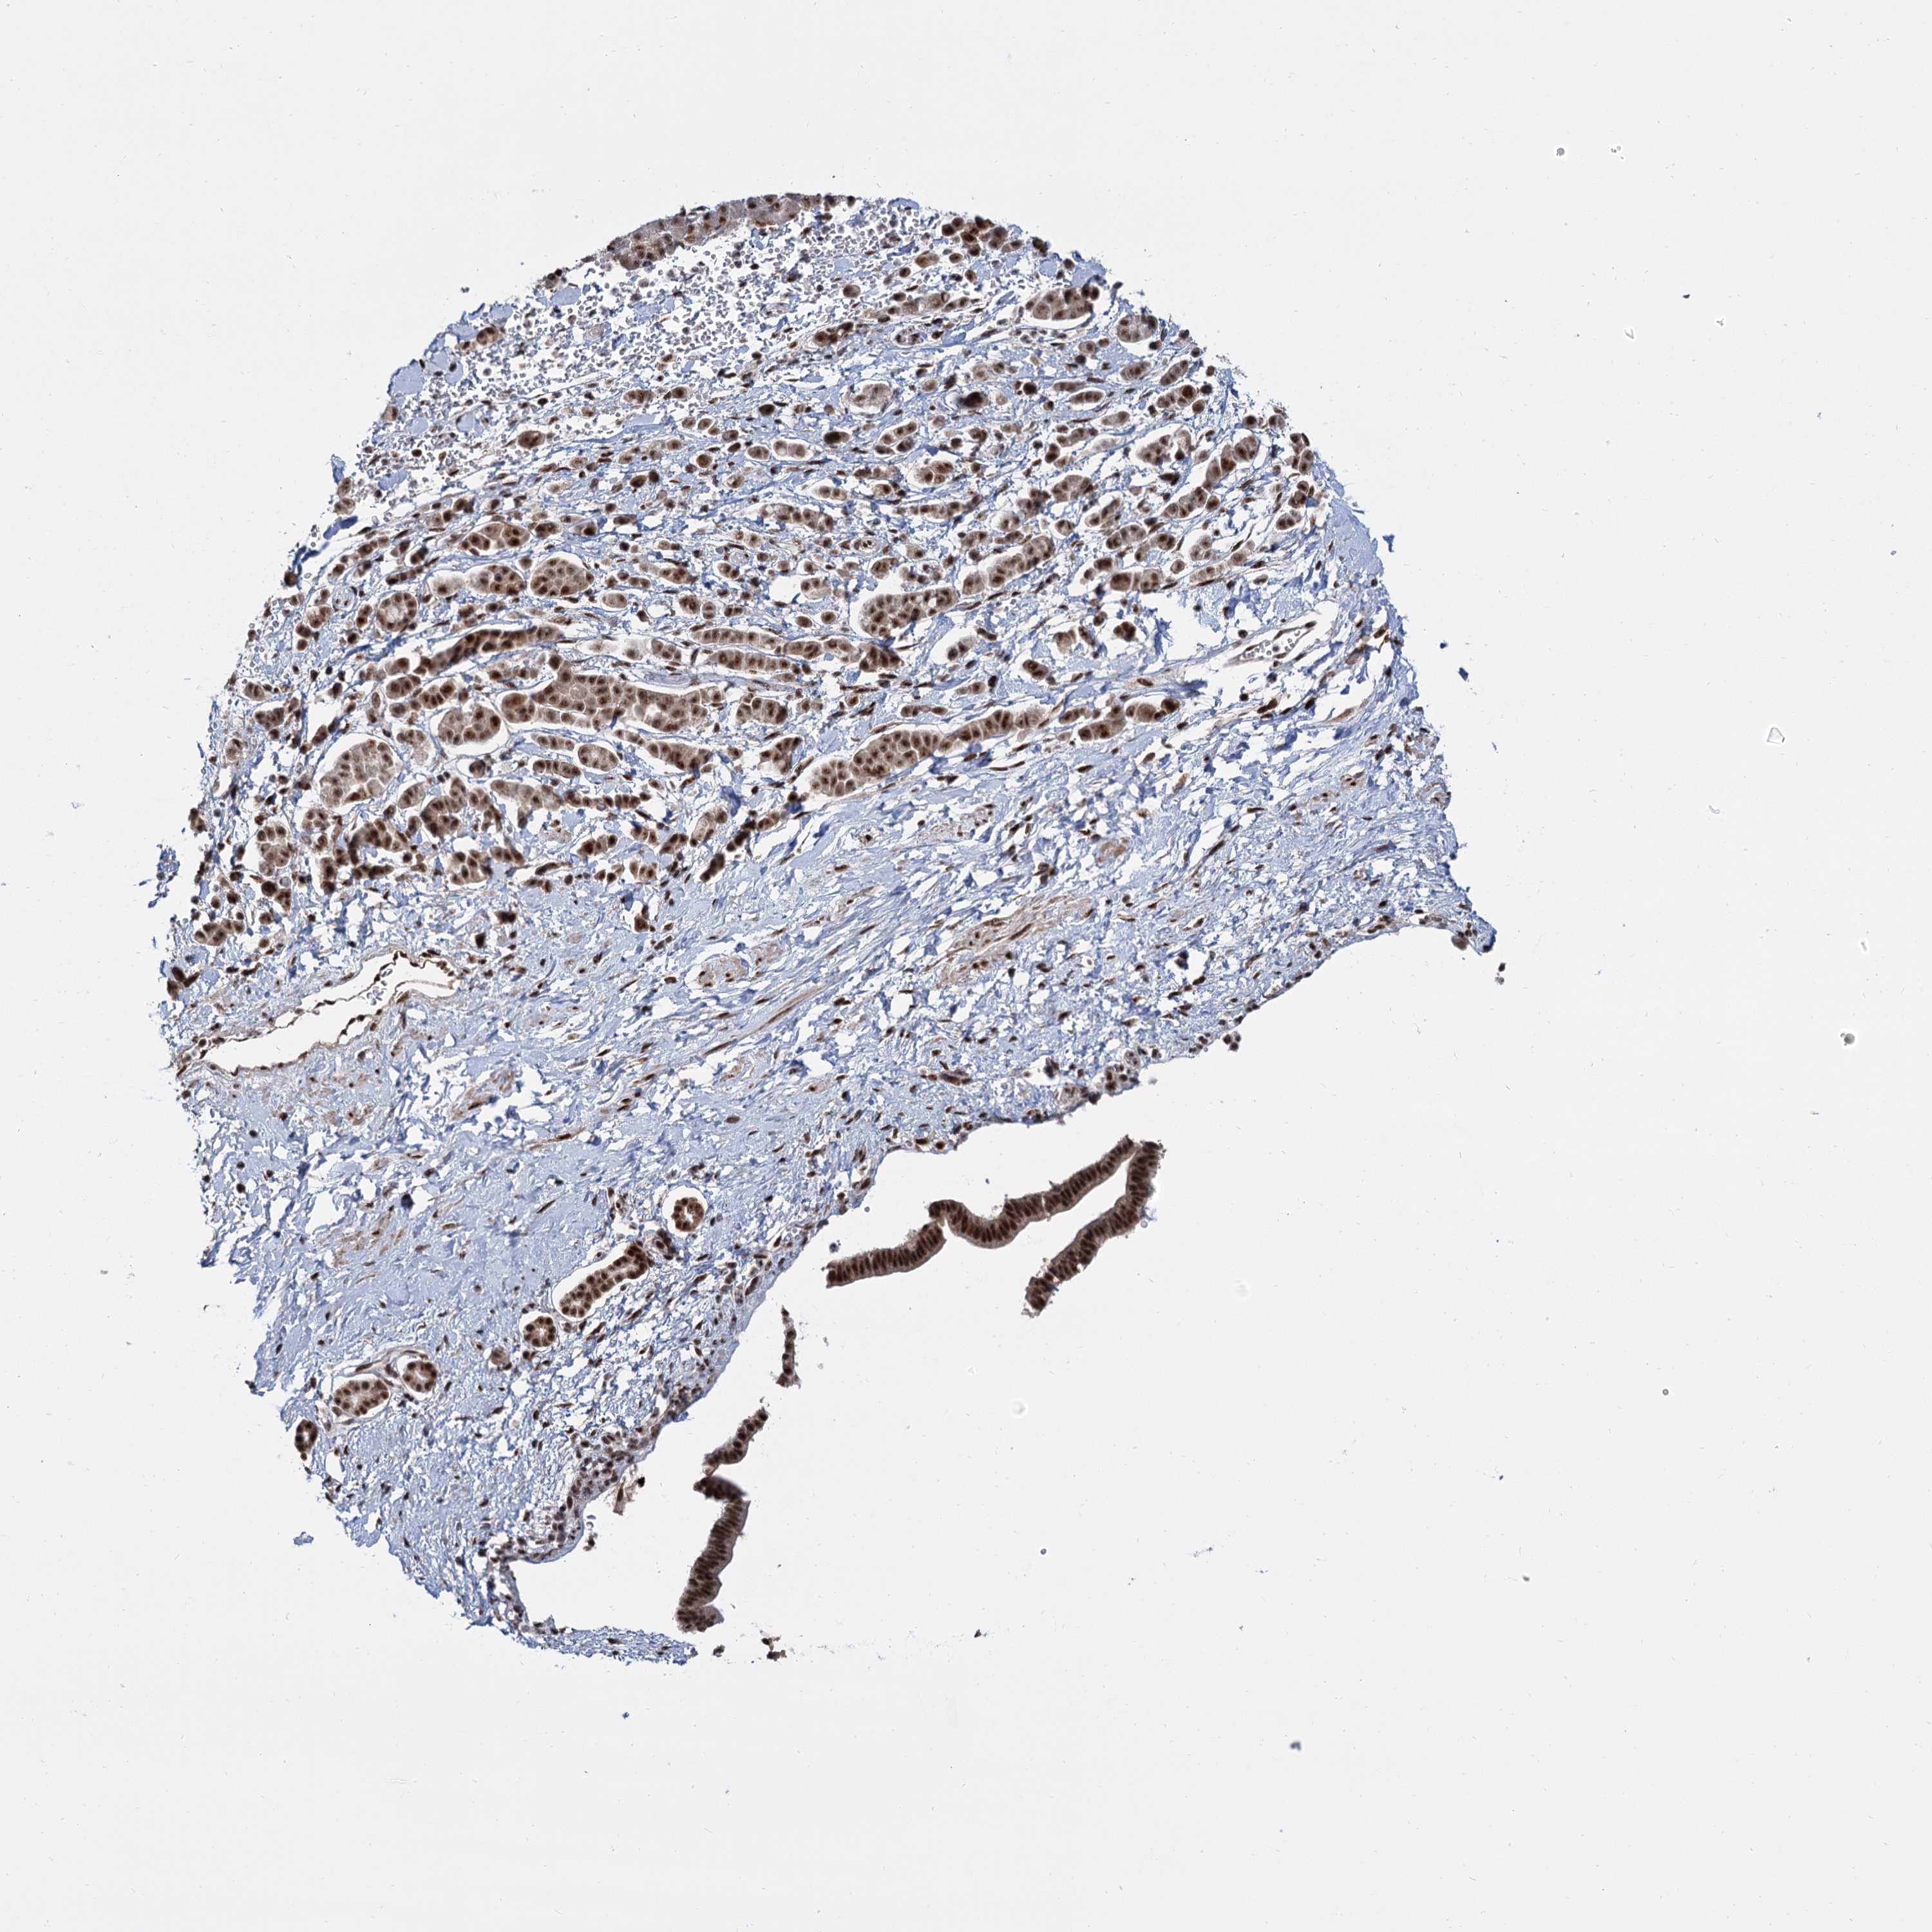

PANCREATIC CANCER - Protein expressioni

A mouse-over function shows sample information and annotation data. Click on an image to view it in a full screen mode. Samples can be filtered based on level of antibody staining by selecting one or several of the following categories: high, medium, low and not detected. The assay and annotation is described here.

Note that samples used for immunohistochemistry by the Human Protein Atlas do not correspond to samples in the TCGA dataset.

Antibody stainingi

Antibody staining in the annotated cell types in the current human tissue is reported as not detected, low, medium, or high, based on conventional immunohistochemistry profiling in selected tissues. This score is based on the combination of the staining intensity and fraction of stained cells.

Each image is clickable and will lead to virtual microscopy that enables deeper exploration of all samples and also displays staining intensity scores, fraction scores and subcellular localization as well as patient and tissue information for each sample.

Antibody HPA038965

Staining

High

Medium

Low

Not detected

Intensity

Strong

Moderate

Weak

Negative

Quantity

>75%

75%-25%

<25%

None

Location

Nuclear

Cytoplasmic/membranous

Cytoplasmic/membranous,nuclear

Adenocarcinoma, NOS